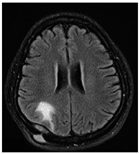

| Sequence | Sequence Characteristics | Main Clinical Distinctions | Example * |

|---|---|---|---|

| T1w | Uses short TR and TE [64] |  | |

| T2w | Uses long TR and TE [64] |  | |

| ceT1w | Uses the same TR and TE as T1w; employs contrast agents [64] |

|  |

| FLAIR | Uses very long TR and TE; the inversion time nulls the signal from fluid [67] |  |